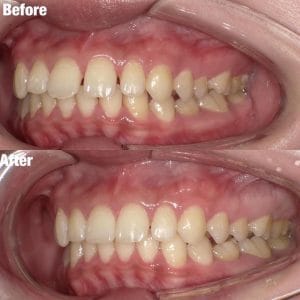

ワイヤー矯正

Case006 – ワイヤー矯正

片顎抜歯を行い、主に上の前歯の歯並びを矯正した症例です。

Case005 – ワイヤー矯正

Case004 – ワイヤー矯正

上下左右4本の抜歯を行い、全体の歯並びを矯正した症例です。

Case003 – ワイヤー矯正

Case002 – ワイヤー矯正

下の歯が前に出てしまう、いわゆる「受け口」を矯正した症例です。

Case001 – ワイヤー矯正